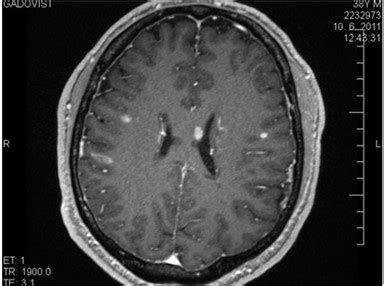

Krvácanie do mozgu u novorodencov (Mozgová hemorágia)

Mozgová hemorágia je odbornejší názov pre krvácanie do mozgu, ktoré môže nastať z rôznych príčin. Jeho závažnosť závisí od miesta a intenzity krvácania a jeho výskyt sa nemusí preukázať hneď. Základné delenie mozgovej hemorágie je na traumatické (poúrazové) a spontánne.

Vnútorné krvácanie bez vonkajšieho vplyvu je zas spôsobené prasknutím cievy v mozgu v dôsledku vysokého krvného tlaku, čo je aj najčastejšou príčinou krvácania do mozgu. Krvácanie môže takisto spôsobiť aneuryzma, teda krvná zrazenina, ktorá upchá cievu a tá následne praskne.

Typy spontánneho krvácania

- Subarachnoidálne krvácanie: Krvácanie do priestoru medzi lebkou a mozgom.

- Intracerebrálne krvácanie: Krvácanie do mozgového tkaniva z artérie.

- Intraventrikulárne krvácanie: Krvácanie sa deje v mozgových komorách.

Typy krvácania v dôsledku úrazu

- Epidurálne krvácanie: Nahromadenie krvi medzi kosťou lebky a tvrdou mozgovou plenou.

- Subdurálne krvácanie: Krvácanie nastane medzi tvrdou mozgovou plenou a tenkou vrstvou pod ňou, zvanou arachnoidea / pavučnica.

Príznaky

Medzi príznaky krvácania do mozgu patrí zvracanie, bolesť hlavy, porucha reči, narušenie správania, strata zraku, poruchy pohybového aparátu, ochrnutie, problémy s prehĺtaním, strata citlivosti, zmätenosť, ospalosť a kóma.

Krvácanie do mozgu u detí

Najčastejšie k nemu dieťa príde úrazom, alebo k nemu dochádza pri predčasne narodených detí a až v polovici prípadov detí, ktoré zomreli na následky syndrómu dychovej tiesne sa takisto objavilo krvácanie do mozgu. Hlavnou príčinou tohto krvácania u predčasne narodených detí je nezrelosť tkaniva a ciev v okolí postranných mozgových komôr.